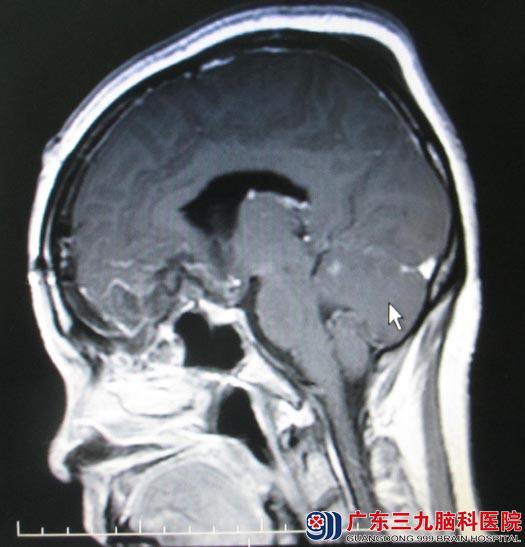

一周前视力下降逐渐加重,当地医院双侧视力及视野检查提示“双眼颞侧视野明显下降”,随后头颅MRI检查提示“前颅窝底占位,直径约5cm,考虑脑膜瘤”;广东三九脑科医院头颅MRI检查结果:前颅窝底占位,直径约5cm,考虑脑膜瘤。

由于肿瘤基底部位于蝶骨平台,往后压迫视交叉,包绕并向后外侧挤压双侧颈内动脉,手术中如何保护颈内动脉及其分支,减少对垂体柄、视神经、下丘脑等重要结构的损伤成为手术的难点。